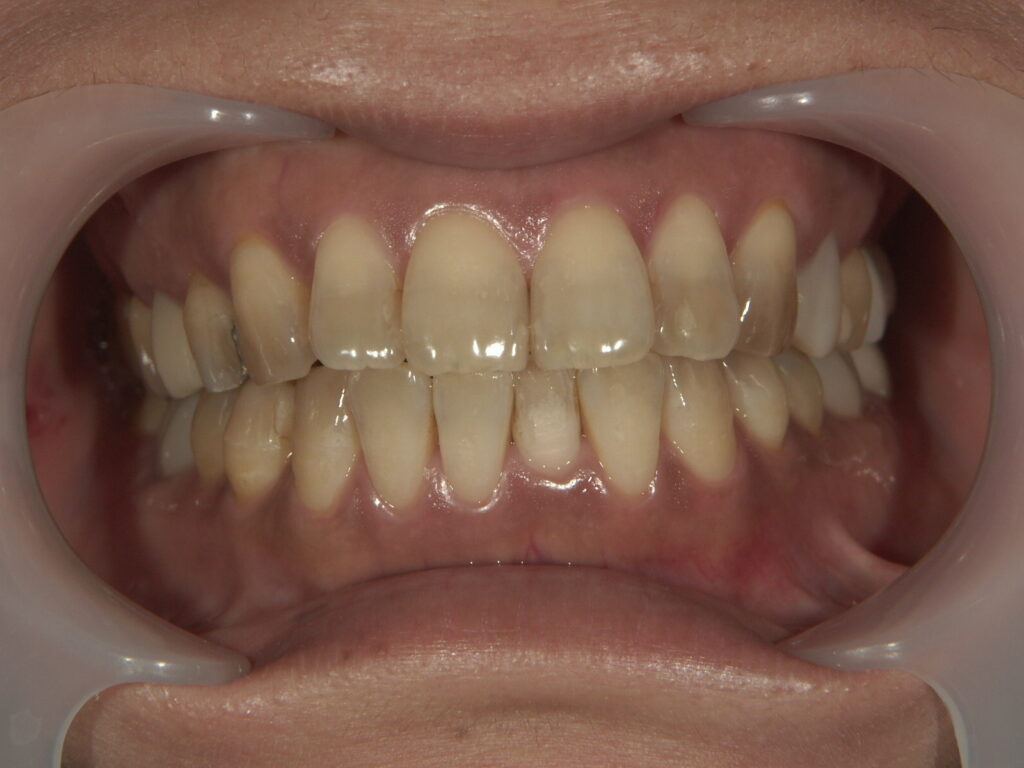

年齢:30代女性